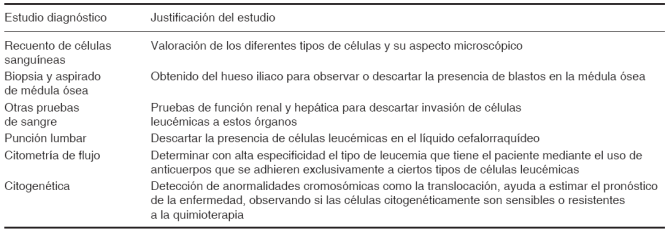

De acuerdo con estudios estadísticos realizados en el 2001 por la Secretaría de Salud en México se registraron alrededor de 13,558 pacientes que fueron ingresados a los hospitales con el diagnóstico de leucemia, de los cuales murieron 232 en un grupo de edad de 1 a 4 años y 558 en el grupo de edad de 5 a 14 años.4,5 La leucemia linfoblástica aguda se caracteriza por aparecer en la primera década de vida; sin embargo, es posible que su frecuencia pueda incrementarse también en pacientes de la tercera edad. Las células inmaduras que en condiciones normales se diferenciarían a cualquier célula del estirpe linfoide o mieloide se le denomina blasto,6 estas células al ser no funcionales no deberían encontrarse en la circulación sanguínea; sin embargo, cuando el paciente debuta con leucemia aparece una producción excesiva de blastos que invaden la médula ósea y por ende, la circulación general. Al producirse una gran cantidad de células inmaduras, éstas ocupan un espacio amplio dentro de la médula ósea de los huesos largos, impidiendo así que las otras células bien diferenciadas puedan reproducirse de forma normal y ocupar su espacio dentro de la médula ósea, generando entonces en el paciente una disminución de todos los conteos celulares (pancitopenia) y además dolor en las extremidades superiores e inferiores. Al tener un descenso importante en el conteo de la hemoglobina y de las plaquetas el paciente cursa con anemia y trombocitopenia que se traduce clínicamente en palidez generalizada, astenia, adinamia y lesiones vasculares en la piel y en la mucosa bucal.5-7 Todo paciente que debuta con leucemia cursa por determinados síndromes asociados, a saber: febril, infiltrativo, hemorrágico, anémico, tumoral y consuntivo (Cuadro I).

El diagnóstico médico de la leucemia se basa en la sintomatología característica y en los estudios de laboratorio que se le indiquen al paciente (Cuadro II). Generalmente para corroborar el diagnóstico se indica un aspirado de médula ósea para valorar si existe o no invasión de blastos, si existe una blastosis medular que supere el 30% de la totalidad celular se podrá emitir dicho diagnóstico. Además de los conteos celulares de la biometría hemática que se caracterizan por tener un conteo elevado de leucocitos (mayor de 50,000 mm3) y la presencia de blastos reportados en la misma, y en consecuencia una disminución importante en el conteo de las plaquetas, neutrófilos, hemoglobina, eritrocitos.

Sin embargo, además de la citogenética existen otros factores que condicionan el pronóstico de la leucemia (Cuadro III).